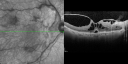

Vitreomacular Traction - Foveal Traction Retinal Detachment

line1.png

9 files, last one added on Sep 19, 2011

Album viewed 849 times